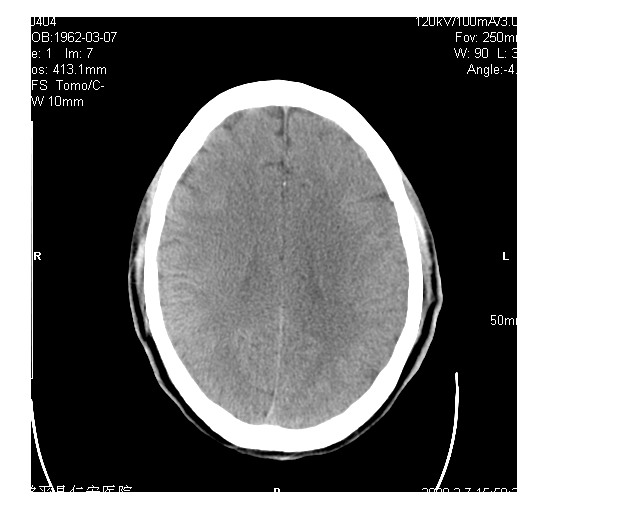

男36岁,外伤进行ct检查时发现脑实质及脑室旁多个细结节状影。是囊虫病吗?

脑内及脑室内可见多发性结节影,脑囊虫病不能除外,建议强化扫描或mri。

有吗?我只看见图象噪声致颗粒粗大,未见异常。建议加大mas

疑脑囊虫病。建议:1)结合临床相关检查;2)必要时行mri检查。

只看到左侧脑室内多发钙化.可以做结合补体实验啊.但未必阳性.还是隔期复查.mr 也未必定啊.